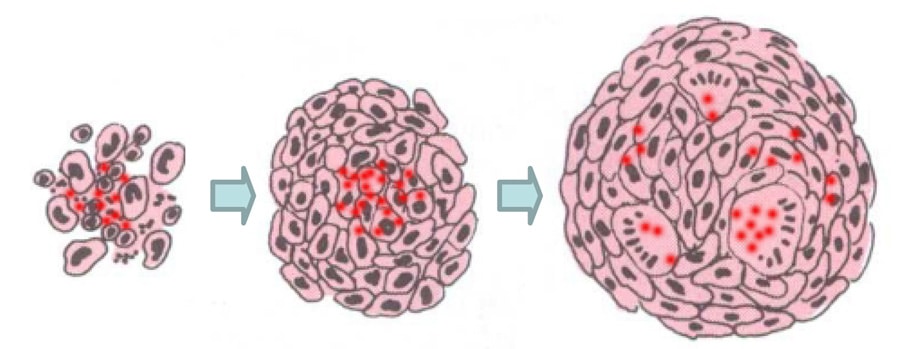

结节病引起球样炎性细胞的集团在受影响的器官发育。这些紧密结合的细胞与细胞间的企业集团被称为肉芽肿是身体的可消化不佳抗原,例如感染,而不是疾病本身免疫反应的产物。

结节病导致P. Acnes.超敏反应组内源性感染内。这就是为什么,在正常情况下,它不会造成问题。但是,它可以作为潜(休眠或隐藏)感染在肺和淋巴结存在。Eishi博士和他的研究小组发现,在一定的环境条件下,休眠P. Acnes.被激活。一旦被激活,P. Acnes.增殖在存在潜在感染的器官的细胞中。在过敏患者中,细菌的增殖触发了肉芽肿的生长。

快速繁殖P. Acnes.并不总是保持在它沉睡的器官局限性。相反,一些细菌可以逃避,通过淋巴系统和血液迅速扩散到身体的其他部位。通过这种快速迁移,P. Acnes.可能最终殖民地殖民,例如,在心脏,眼睛或皮肤中建立新的潜在感染。

新的潜伏感染可能被激活,以同样的方式与原始感染,特定环境条件下。这导致系统性结节病,其中体内多个器官发育肉芽肿。只要人体的免疫系统无法消灭任何潜在的感染,结节病的周期将重复任何时间出现在正确的条件引起细菌激活。